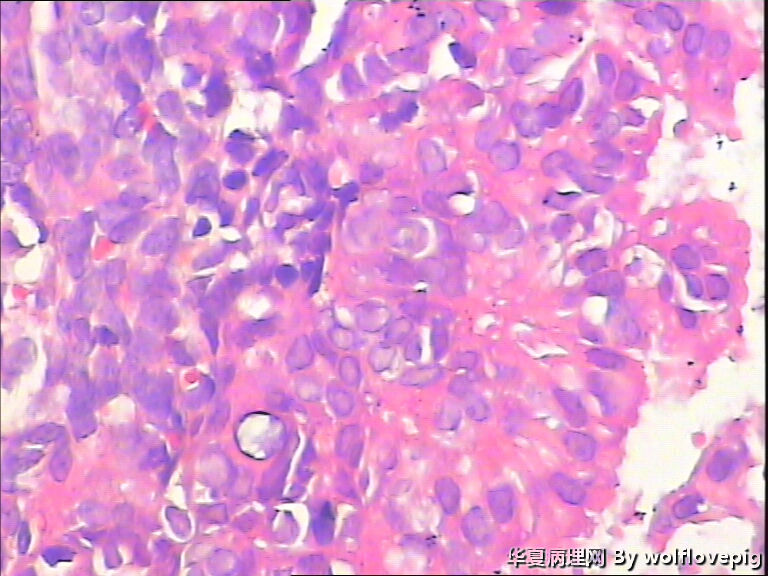

求助,子宫内膜!

48y

子宫内膜复杂性非典型增生(有没有癌变,待制作优良的切片再诊断吧)。

复杂性非典型增生

个人认为有不典型增生。

复杂性非典型增生(EIN)

子宫内膜复杂性非典型增生